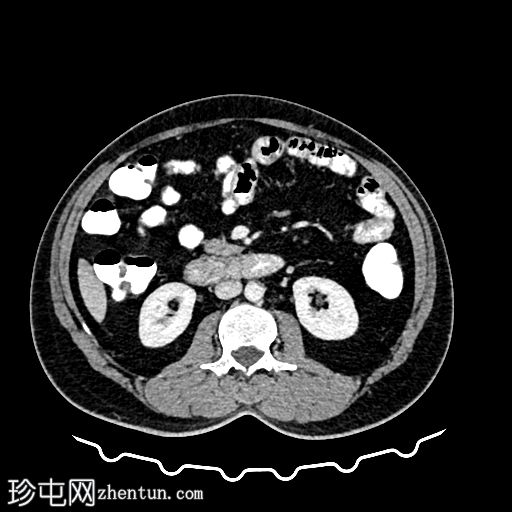

CT

轴位

平扫

轴位增强扫描

动脉期

门静脉期

乙状结肠旁可见两处小的脂肪衰减病灶。较小的病灶呈周边环状强化,伴有轻度邻近脂肪条索状改变 → 急性大网膜垂炎。

较大的病灶呈薄环状强化,周围无炎症 → 消退期/慢

性病

变。未见肠壁增厚,未见肠腔相通,无游离液体或积液。

大网膜垂炎是指由于扭转或静脉血栓形成引起的大网膜垂缺血性炎症,最常见于乙状结肠旁。 CT

影像

具有特征性,有助于避免不必要的抗生素或手术。